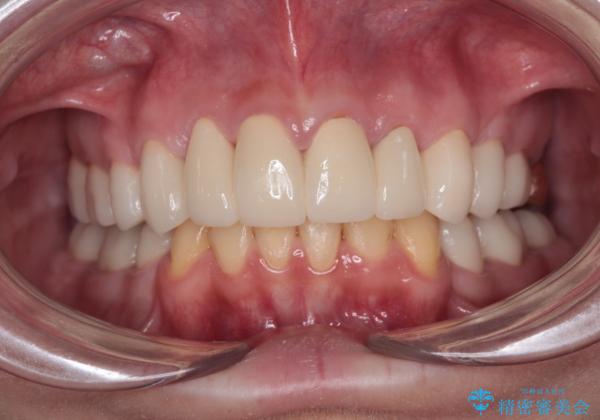

酸蝕歯でボロボロの歯の審美歯科治療 矯正治療も併用して、美しい口元へ

- 一時期の拒食症に伴い歯が酸で溶けてボロボロになってしまったとのことで来院された患者様です。

酸によりエナメル質の大半が溶けており、下顎前歯以外は酷いむし歯のような状態でした。

矯正治療終了後に、残った歯をオールセラミッククラウンにて補綴治療を行うこととしました。

途中来院が困難な時期があったり、歯周外科処置を行って治癒を待ったりと、治療期間は長くなりましたが、初診時とは比べものにならないくらいきれいに仕上げることができました。